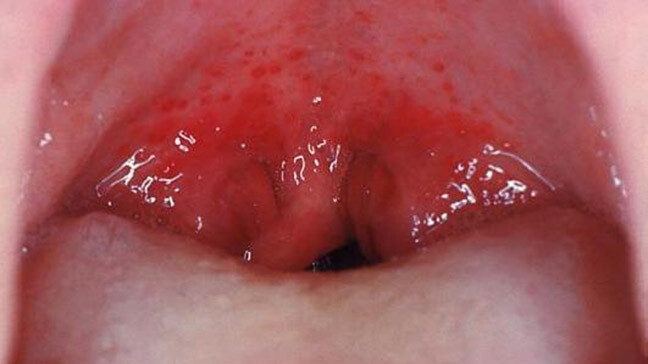

What Causes Red Spots On The Roof Of Your Mouth?

Red spots on the roof of your mouth can be caused by a variety of different reasons. Some are just a minor inconvenience, while others could be a sign of a more serious health issue that may require further investigation. Here are some common possibilities:

Candidiasis

Also known as thrush or oral candidiasis, this fungal overgrowth can cause red bumps and white patches inside the mouth. Common in those with dentures and diabetes, candidiasis is most often treated by preventing the overgrowth in the first place. According to the ADA, oral antifungals may also be used to combat particularly tough cases. Learn more about thrush in the Colgate Oral Care resources.